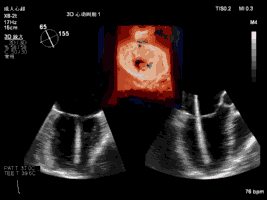

夹合术中:三维心超示输送鞘跨瓣